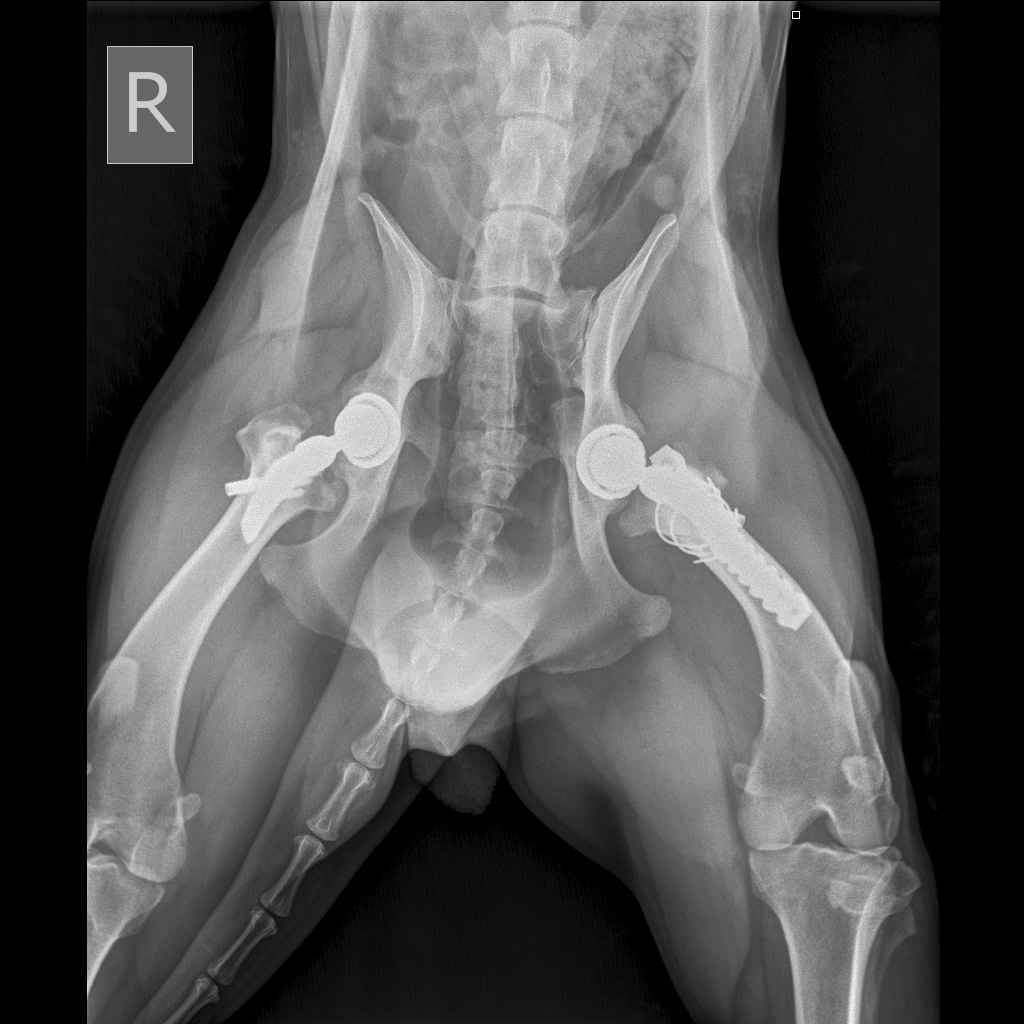

Вчера резко захромал, встал на 3 ноги и понос.

По рентгену чисто

В понедельник КТ